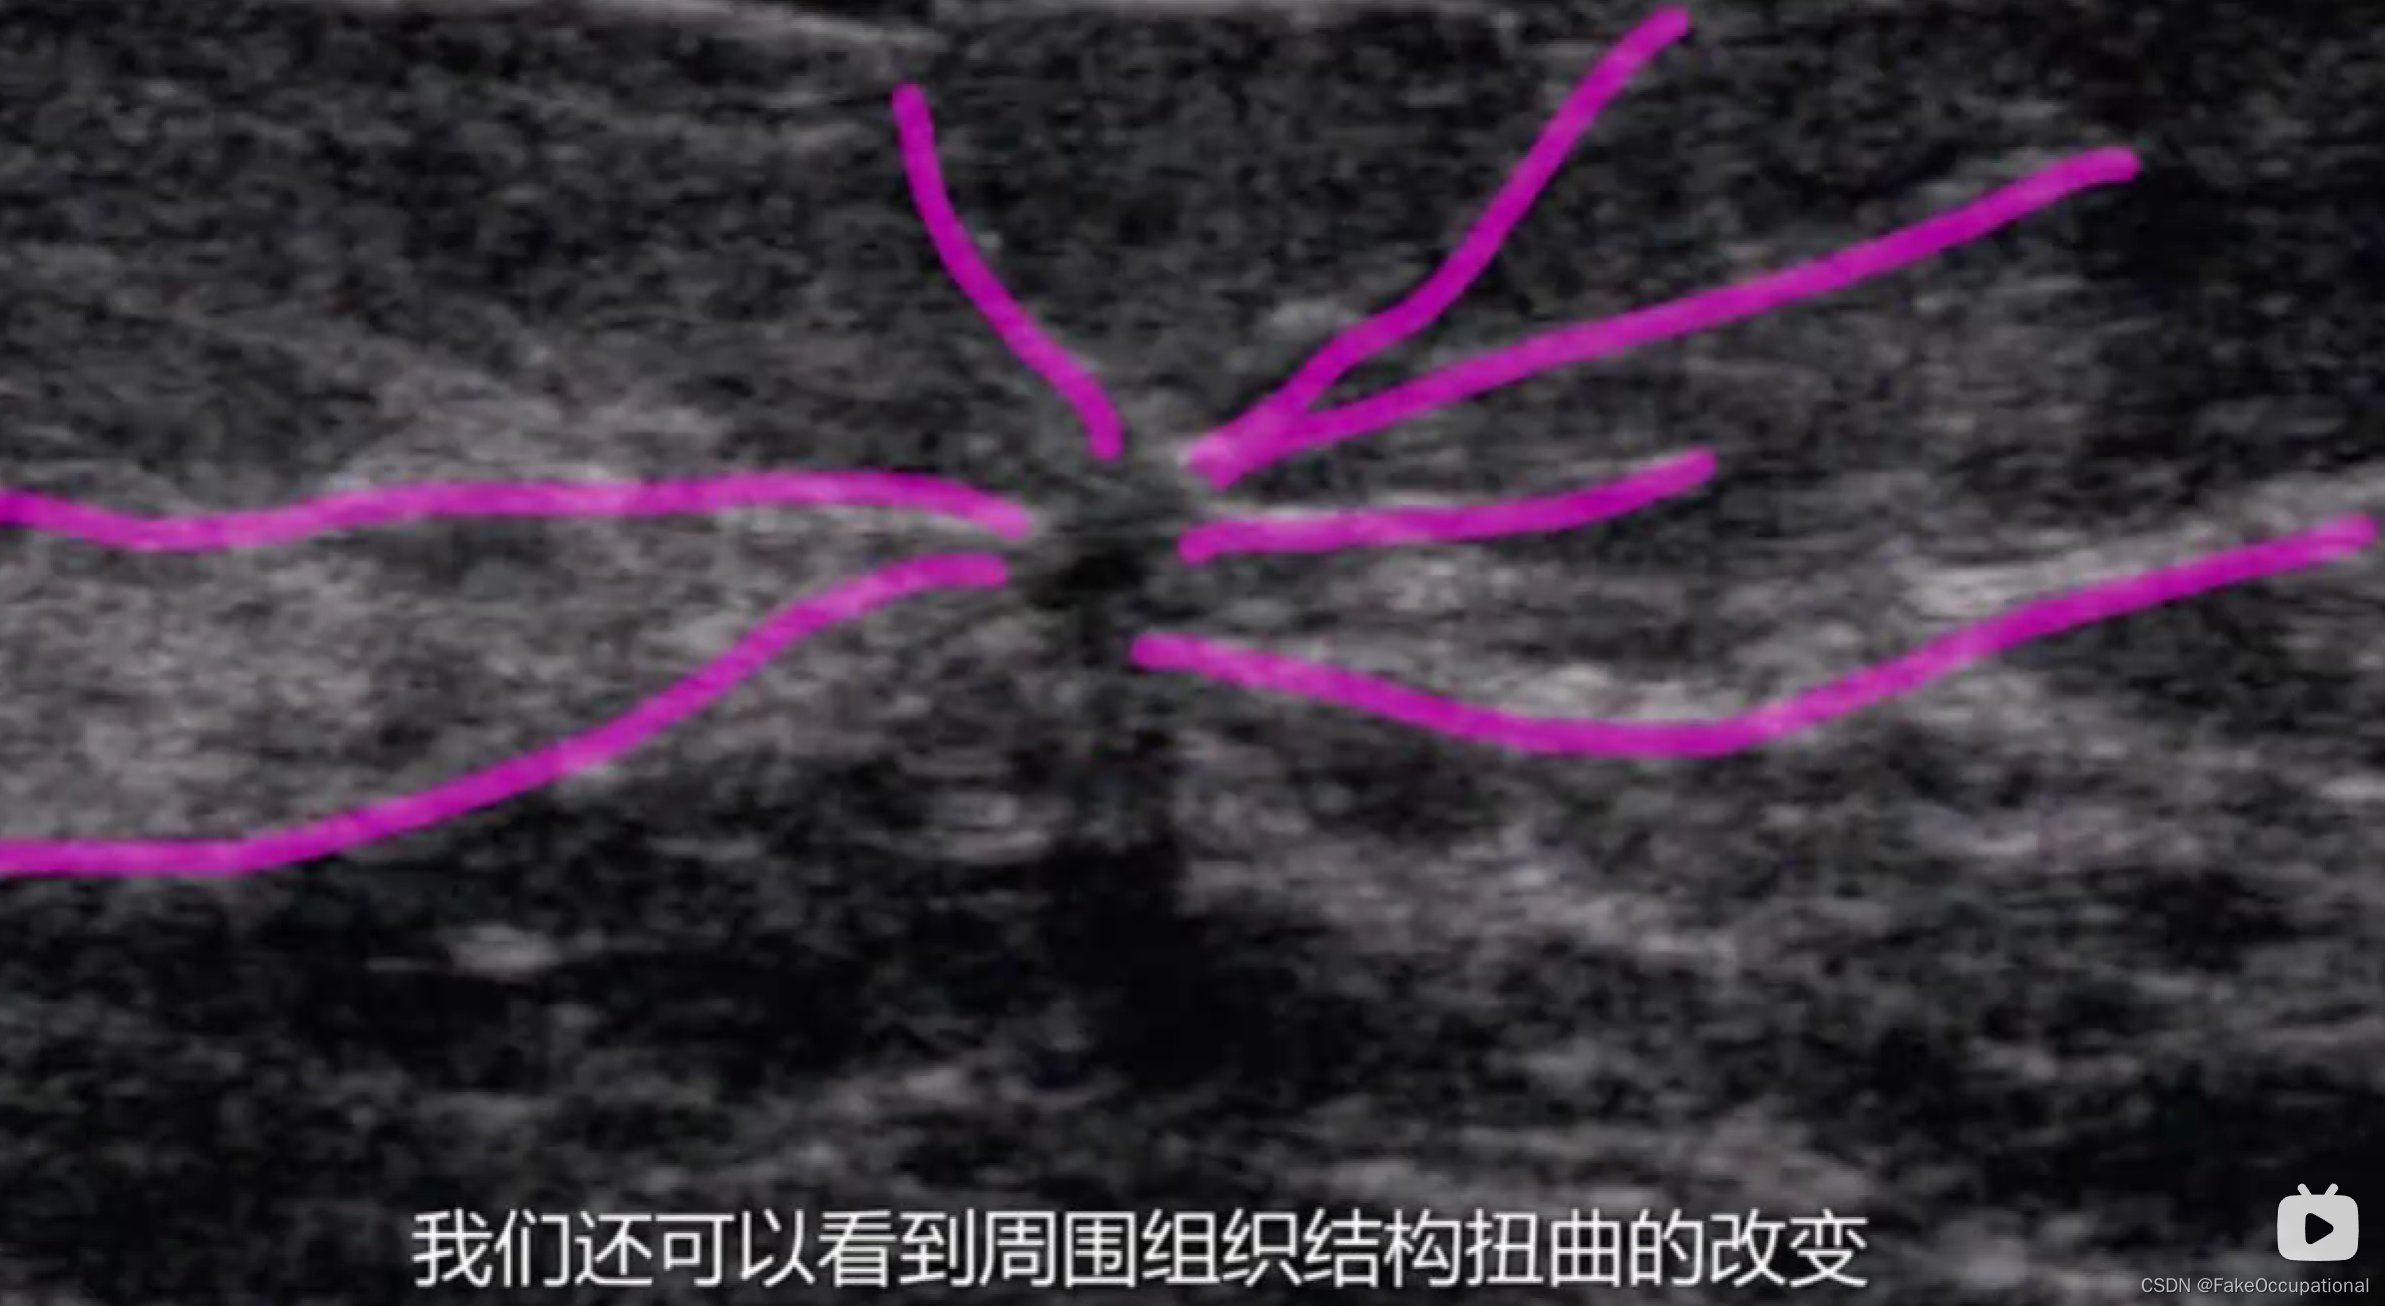

乳腺癌

- 其理论依据是恶性肿瘤常星离心性生长